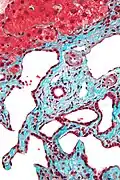

Fucsina ácida

La fucsina ácida puede ser utilizada para colorear colágeno, músculo liso o mitocondrias. Forma parte de la coloración tricrómica de Mallory donde se utiliza para colorear núcleo y citoplasma. En la tinción de Van Gieson (picrofucsina), la fucsina es la responsable de dar el color rojo a las fibras de colágeno. También es una coloración tradicional para colorear mitocondrias (método de Altmann).